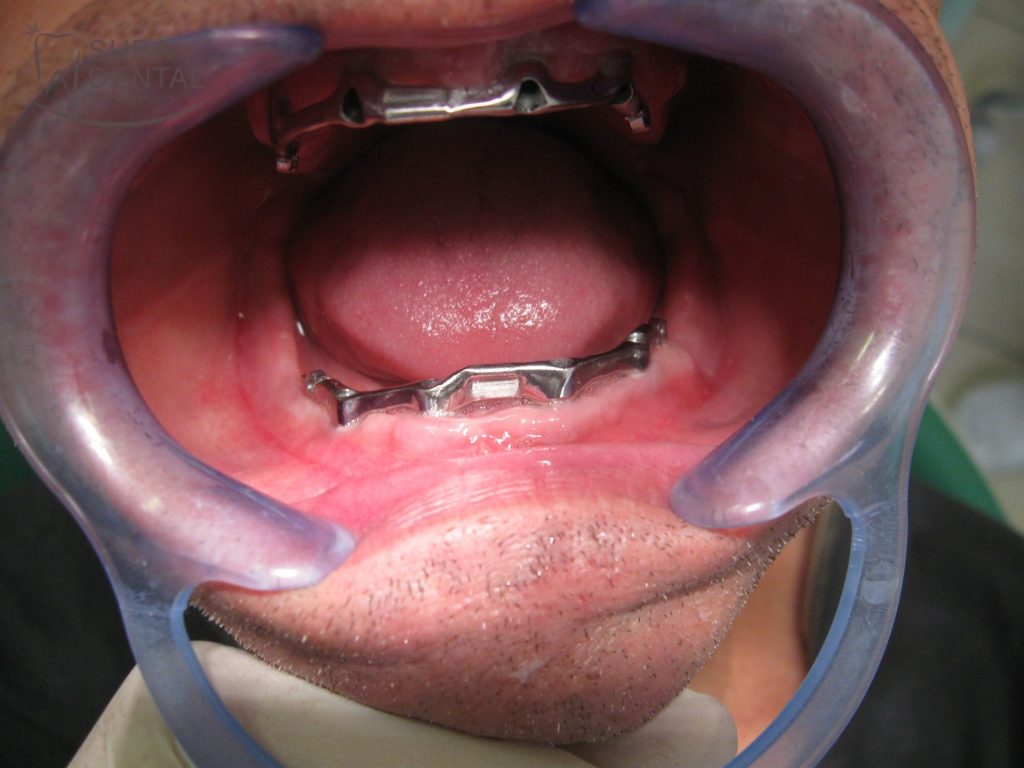

A stégpróba során az elkészült stéget a helyére, azaz az implantátumokba csavaroztuk a gyógyulási csavarok eltávolítása után, hogy ellenőrizni tudjuk a fogpótlás vázának pontosságát.

Alsó 4 implantátumra készült stég szájban